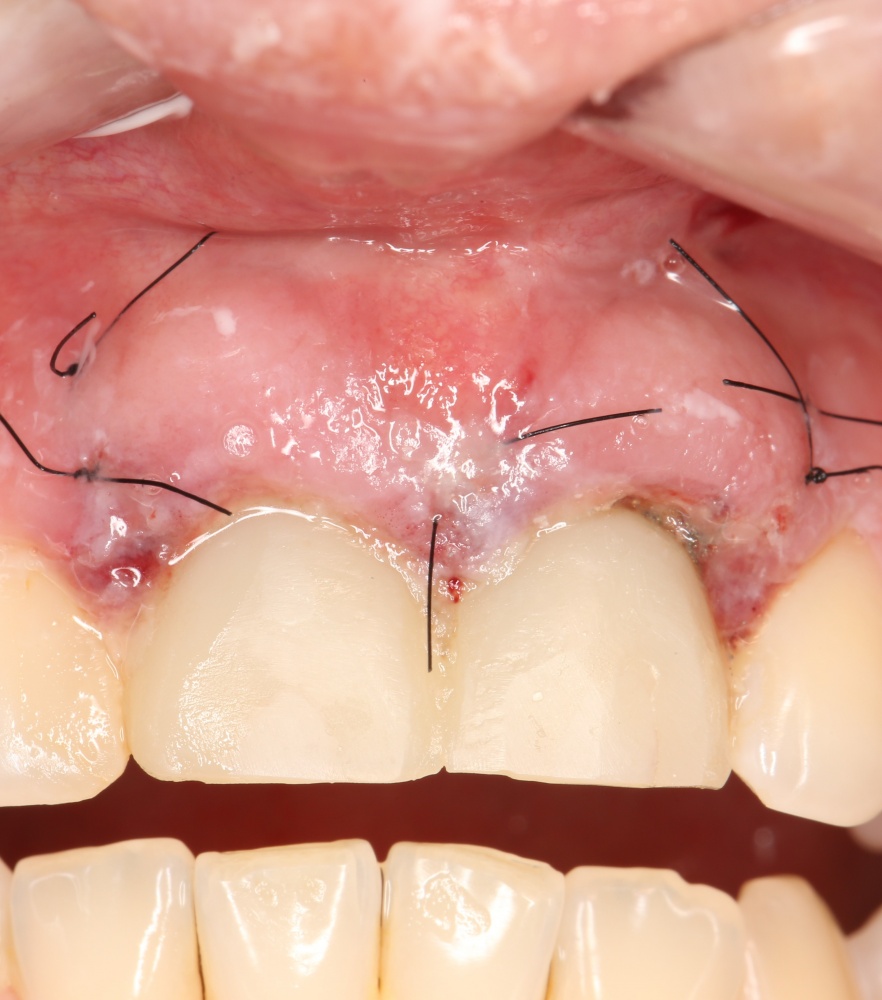

Рекомендации по установке имплантов. Для всех. Часть V.